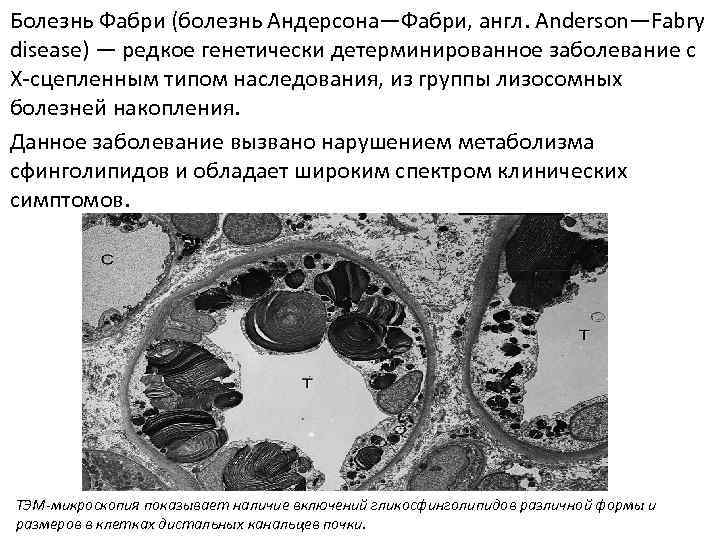

Болезнь Фабри (болезнь Андерсона—Фабри, англ. Anderson—Fabry disease) — редкое генетически детерминированное заболевание с Х-сцепленным типом наследования, из группы лизосомных болезней накопления. Данное заболевание вызвано нарушением метаболизма сфинголипидов и обладает широким спектром клинических симптомов. ТЭМ-микроскопия показывает наличие включений гликосфинголипидов различной формы и размеров в клетках дистальных канальцев почки.